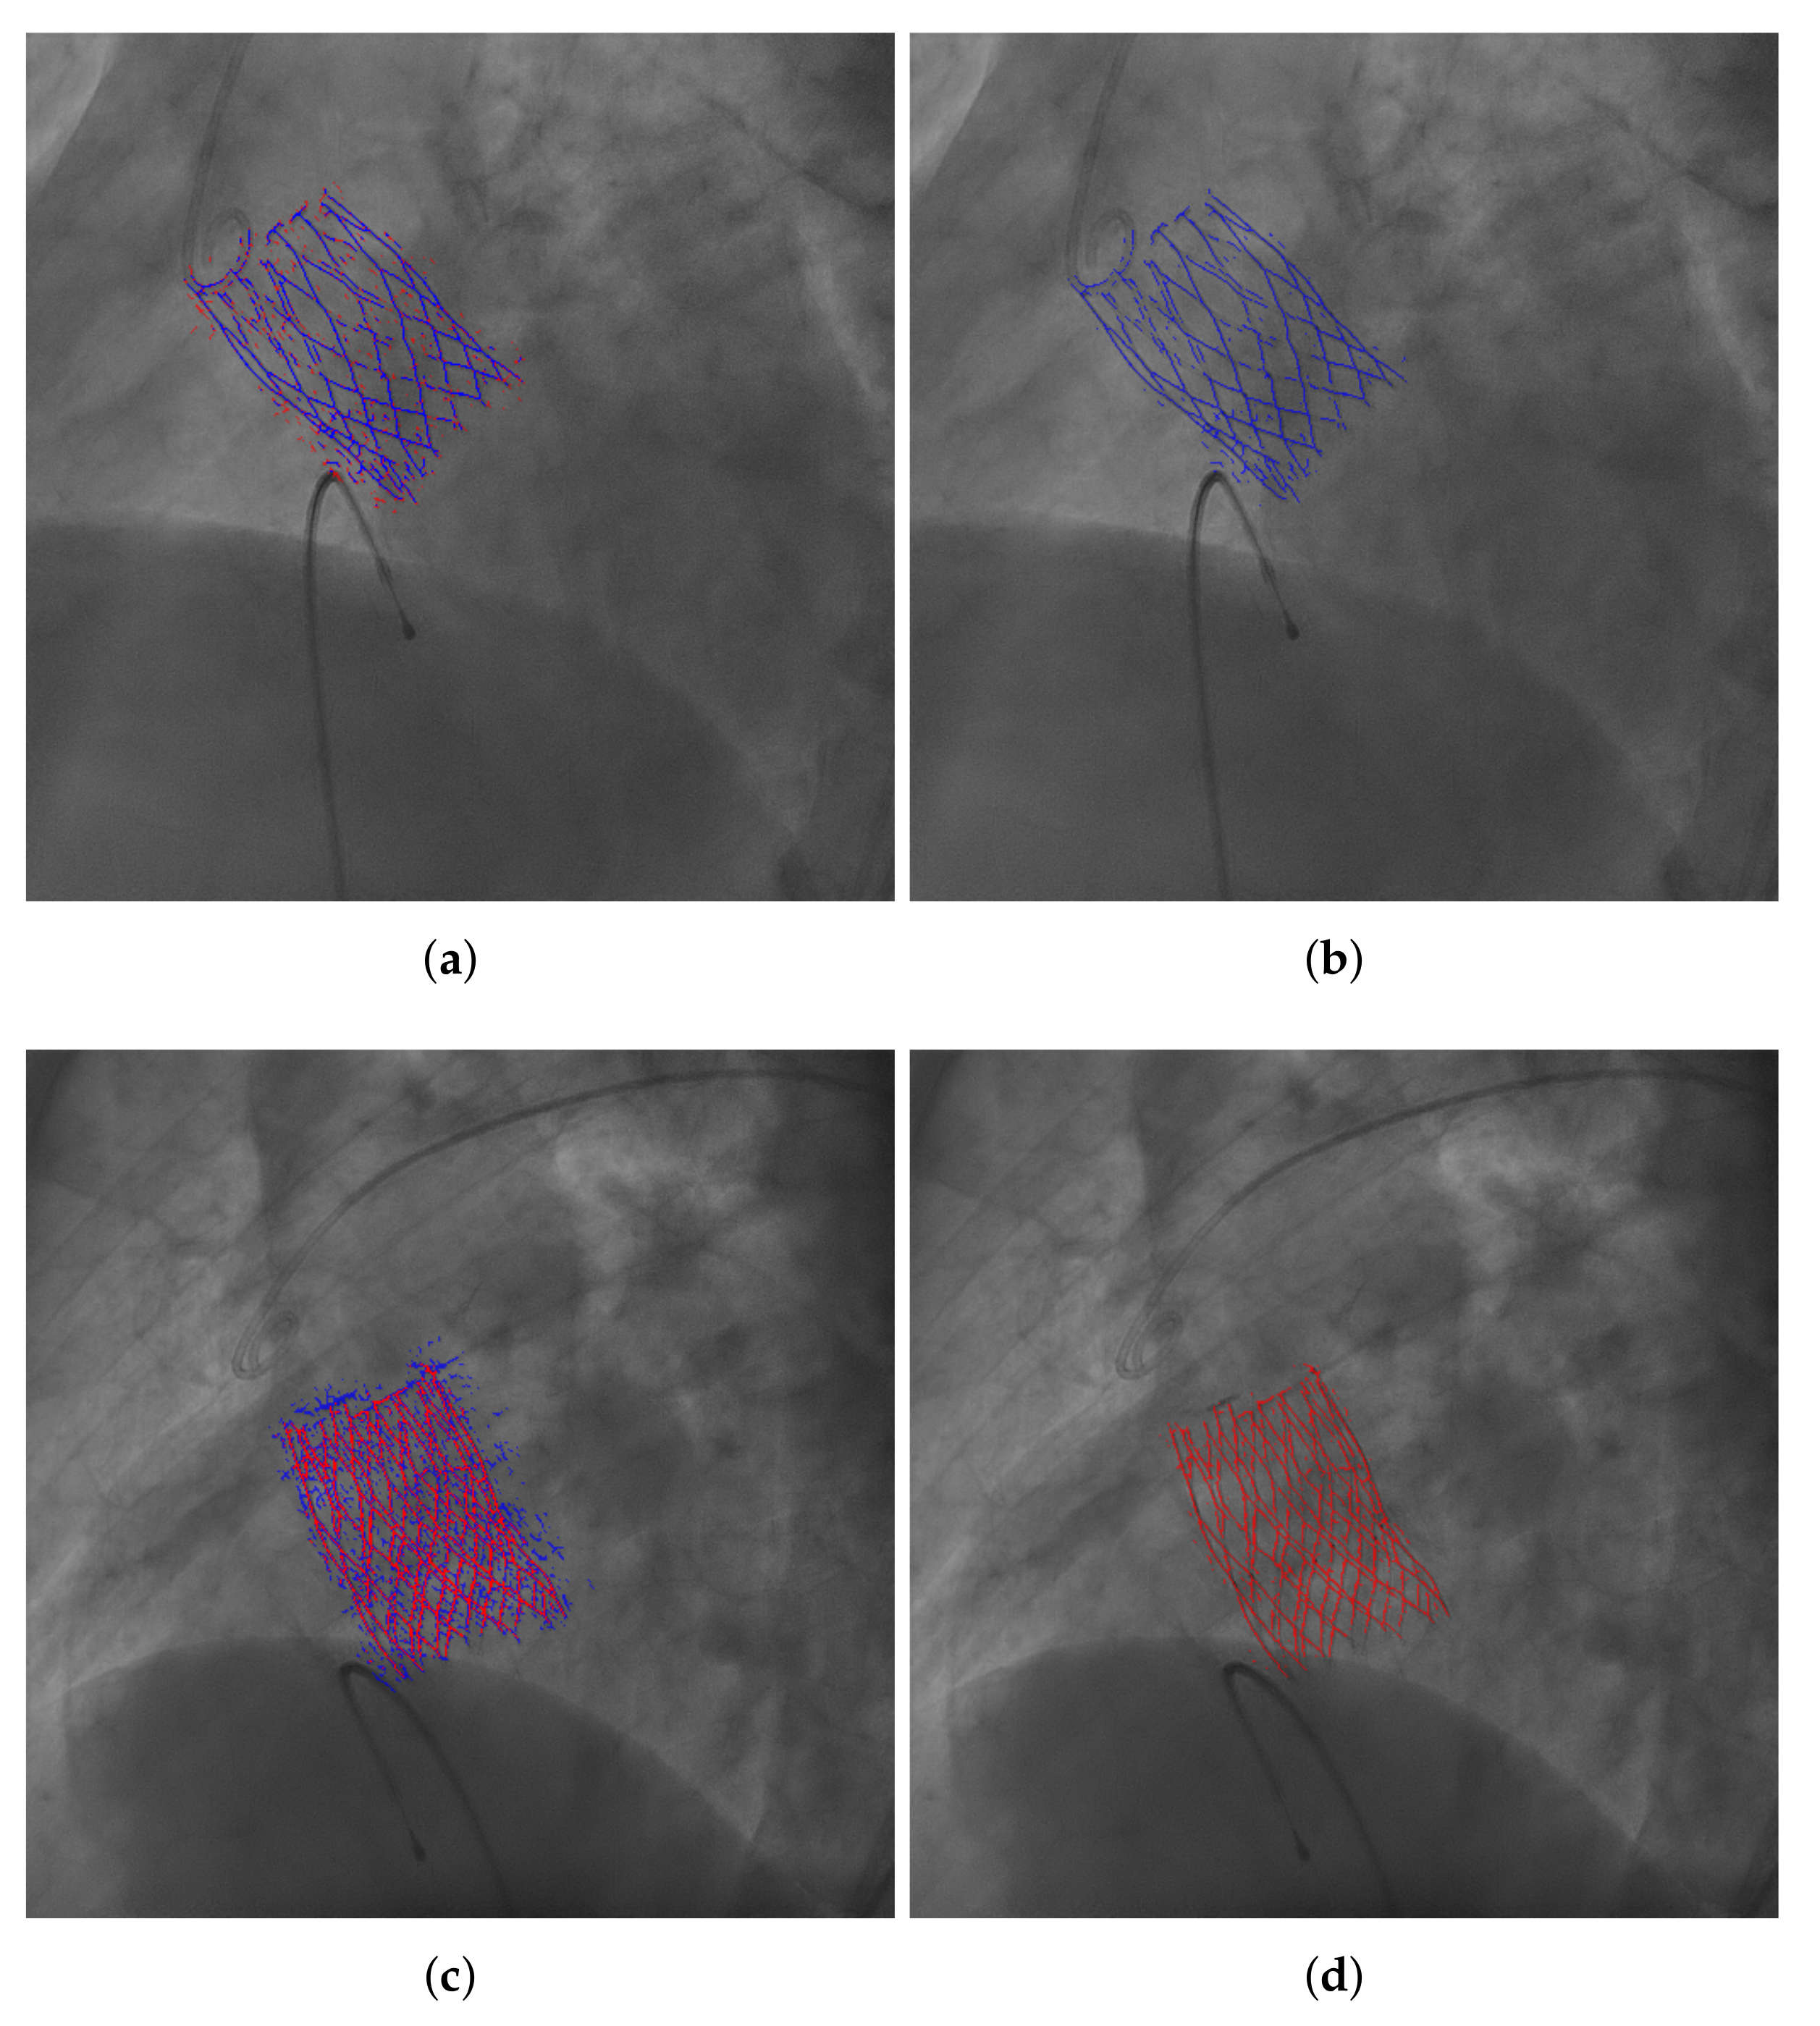

3.1. Image Acquisition and Annotation

3.3. THV Segmentation

4.2. Evaluation of the Results of the Selected Model